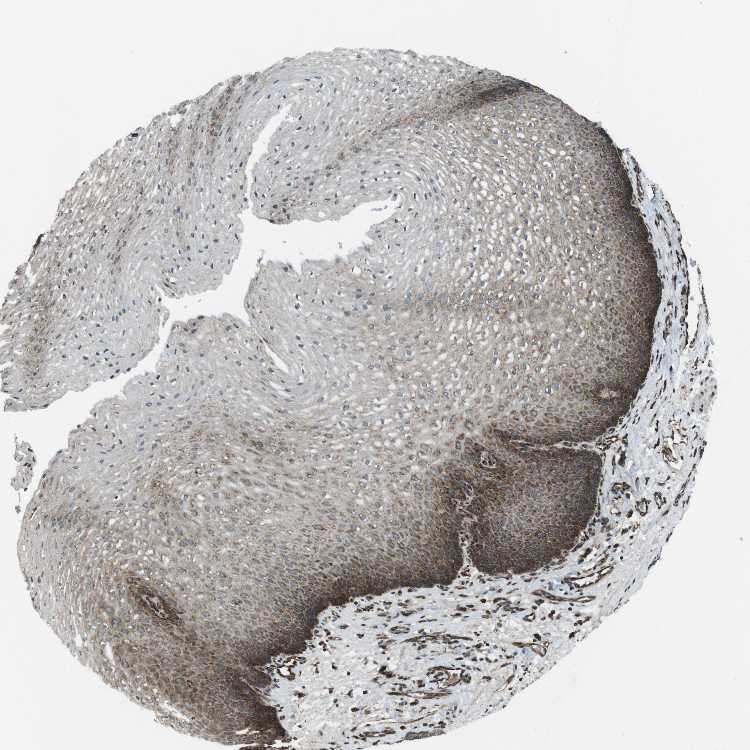

ESOPHAGUS - Antibody stainingi

Antibody staining in the annotated cell types in the current human tissue is reported as not detected, low, medium, or high, based on conventional immunohistochemistry profiling in selected tissues. This score is based on the combination of the staining intensity and fraction of stained cells.

Each image is clickable and will lead to virtual microscopy that enables deeper exploration of all samples and also displays staining intensity scores, fraction scores and subcellular localization as well as patient and tissue information for each sample.

Antibody HPA003178Antibody HPA017876Antibody CAB015331

Squamous epithelial cells MediumMediumHigh